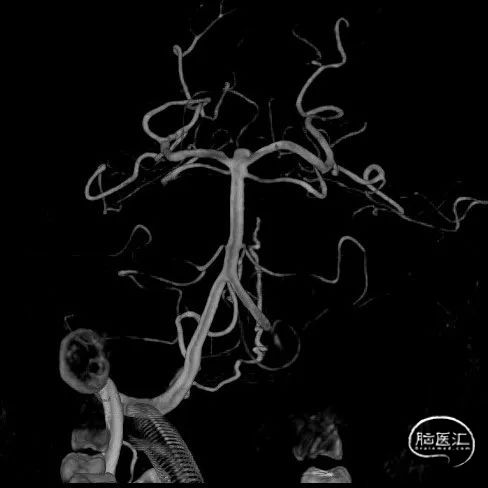

左侧A1、基底动脉尖动脉瘤

左侧大脑前动脉瘤2.97*1.32mm

基底动脉尖动脉瘤3.44*2.47mm

左侧大脑前动脉动脉瘤DSA正侧位

基底动脉尖动脉瘤DSA正侧位